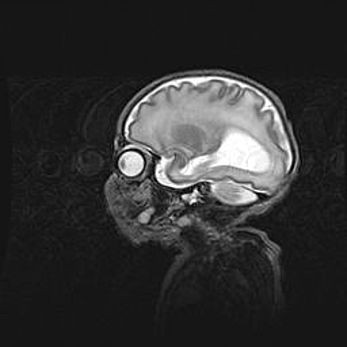

Неполная лизэнцефалия (пахигирия). Открытая гидроцефалия.

Возраст: 17 дней

Вес: 3110 г

Пол: мужской

Окружность головы: 33,5 см

Срок гестации: 35-36 недель

Лизэнцефалия—недоразвитие корковой пластинки и мозговых извилин в результате нарушения миграции нейронов коры. Поверхность мозговых полушарий гладкая. Микроскопически выявляется отсутствие нормальных слоев коры и скопление групп нейронов в подкорковом белом веществе.

Пахигирия—уменьшение числа вторичных извилин. В пораженном полушарии нервные клетки образуют толстый недифференцированный слой с неправильно расположенными нервными волокнами и группами гетеротопных клеток. Нервные клетки незрелые. Белое вещество истончено. При этом нередко аномально развит корково-спинномозговой путь.